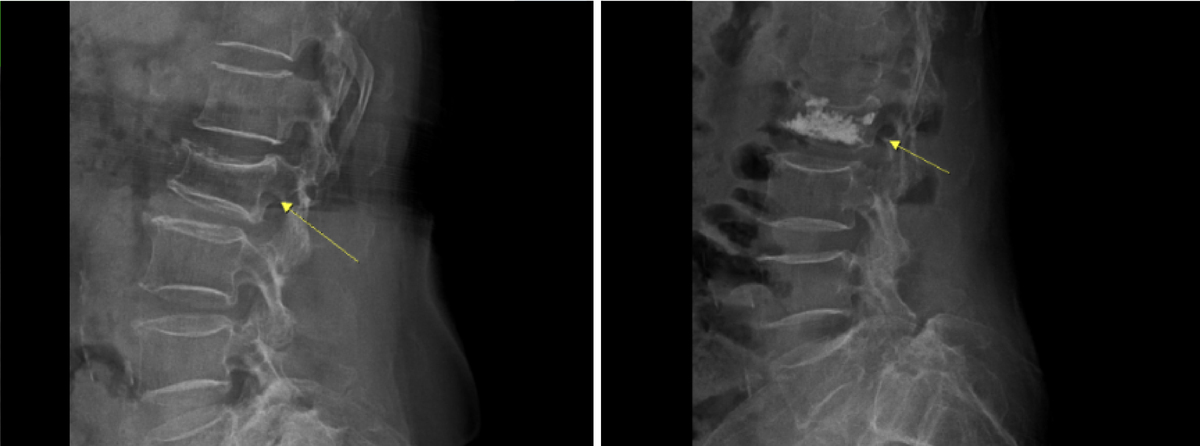

진단은 단순 X선으로 척추체의 높이 감소와 쐐기 변형 여부를 확인하고, MRI로 골수부종과 신경 압박 여부를 평가한다. 골밀도검사를 통해 골다공증 여부를 확인해 재골절 위험을 줄이기 위한 약물치료 계획을 세운다.

보존적 치료에도 호전이 없거나 통증이 심할 경우 척추체 성형술이 대안이 된다. 국소마취하에 특수 바늘을 골절 부위에 삽입해 골시멘트를 주입, 척추체를 안정화하는 방식이다. 풍선복원술은 함몰된 공간을 들어 올린 뒤 시멘트를 주입해 높이를 회복시키는 방법이다.